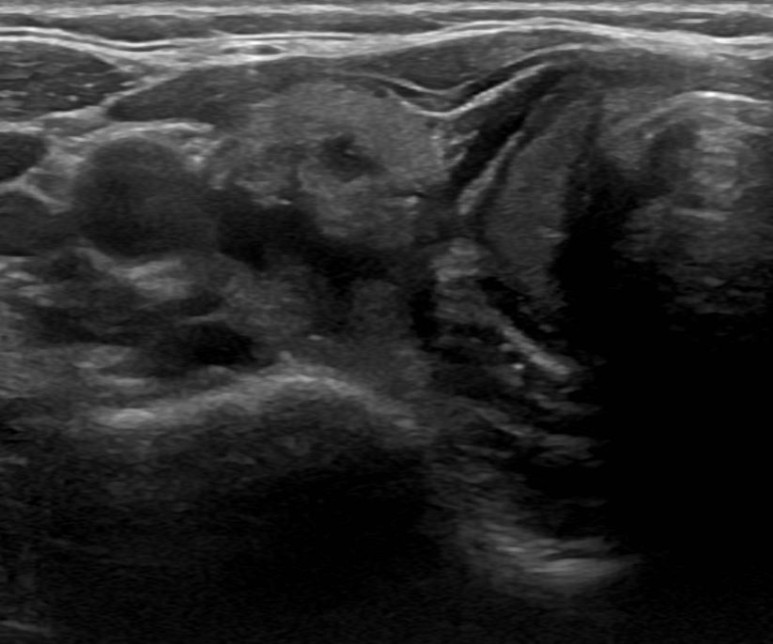

여포성 종양(follicular neopl asm, 소포신생물)이 의심되어 세침흡인검사를 실시하고

다행히도 베세다 시스템II에서 양성결절로 추적을 할 예정입니다

여포성 종양(follicular neoplasm)이라는 선종(aemoma)은 갑상선 결절의 5~10% 정도를 차지하며 여포성 종양(follicular neoplasm. 혹은 소포신생물)과 허들세포 선종(Hurthle celladenoma) 등이 있습니다. 세포소견만으로는 여포성 종양과 여포성 암(foillcular cancer)을 구별할 수 없으므로 세침흡인 검사에서 여포성 종양(follicular neoplasm)이 진단된 경우 수술을 통해 확인해야 합니다.